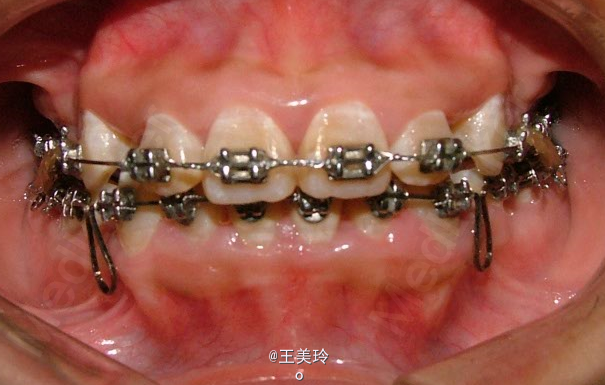

主诉:面突求矫治 既往史:无矫治史,无牙科治疗史,无外伤史,无过敏史,无口腔不良习惯,无家族遗传史 口腔检查:恒牙列,A7-B7;C7-D7。个别牙齿不齐 尖牙磨牙I类关系轻度深覆合深覆盖 下颌中线右偏约2mm 双颌前突,突面型 关节无弹响无压痛

诊断:安氏I类双颌前突 矫治计划 1.MBT矫治技术 2.拔牙矫治,拔A4B4C4D4 3.闭隙曲,J勾内收前牙 4.矫治结束后尖牙,磨牙,覆合覆盖正常 5.面型有所改善